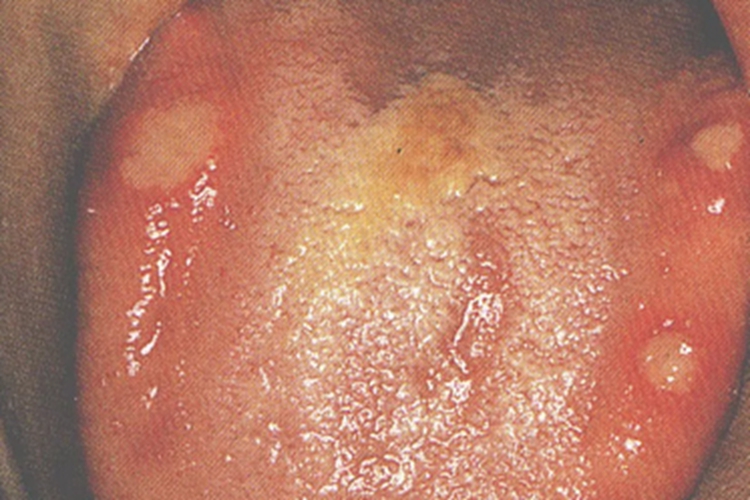

一般表现为反复发作的圆形或椭圆形溃疡,表现出类似舌头起泡的症状,具有“黄、红、凹、痛”的临床特征,即溃疡表面覆盖黄色假膜、周围有红晕带、中央凹陷、疼痛明显。

口腔单纯疱疹水疱期可表现为口腔黏膜出现成簇小水疱,也可能出现在舌上,表现为舌头起泡。水疱疱壁薄、透明,易溃破,形成浅表溃疡。